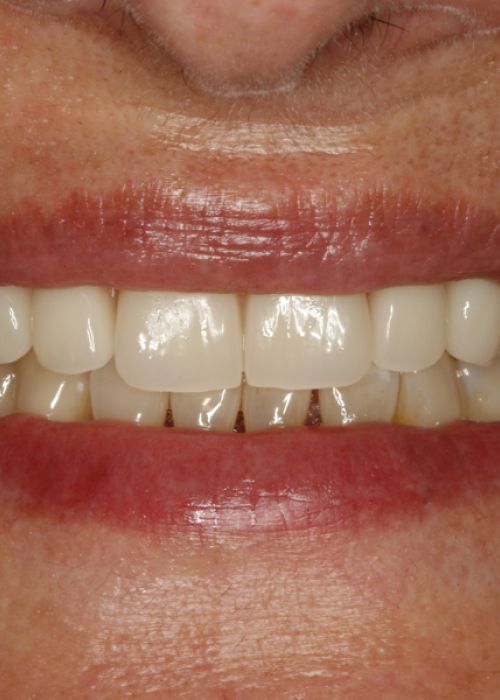

Resolución de un caso con implicación estética en el sector antero-superior. A propósito de un caso